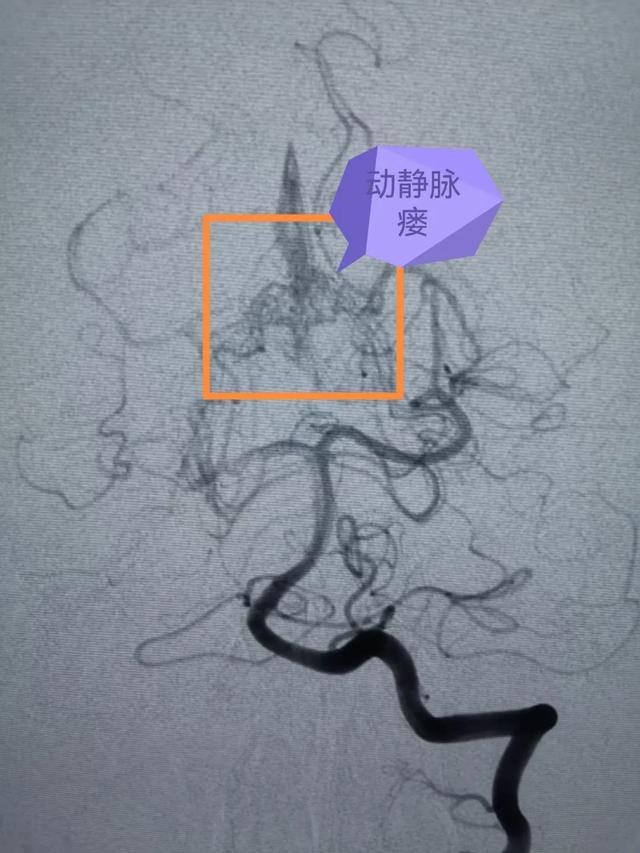

但是脑血管疾病种类较多,形态多样,头颅MR仍然无法进一步确诊,诊断脑血管疾病的“金标准”则是全脑血管造影(DSA),海西州人民医院此前已经具备了此项特殊检查的硬件设施和人员配备。巴特尔副主任医师更是在2年前就在浙大一院进修学习掌握了全脑血管造影技术。于是,他随后即带领海西州人民医院的本土团队为大梅顺利开展了全脑血管造影术,术中发现大梅的小脑幕区贴近脑干处,有个直径约1cm、像蚯蚓一样扭曲的脑血管畸形。

术前DSA影像

此时大梅不仅脑干出血,脑部的血管畸形团块由大量细小的动静脉瘘组成,动脉血直接进入静脉,迂曲扩张的静脉在动脉血流的冲击下非常容易再次破裂出血,形成脑内血肿危及生命,手术迫在眉睫。